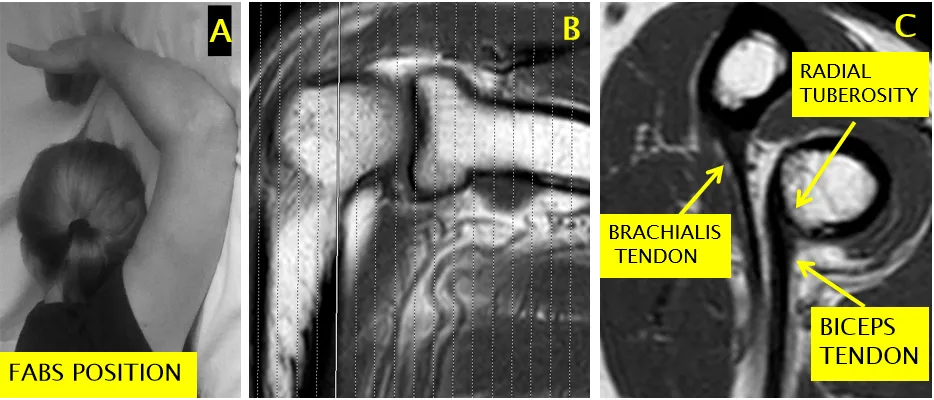

远端肱二头肌腱最佳显示方式

• 采用屈曲外展旋前位(FABS 位):肘关节屈曲、肩关节外展、前臂旋前。

• 矢状面扫描范围应覆盖关节线上方10厘米,以显示可能回缩的肌腱。